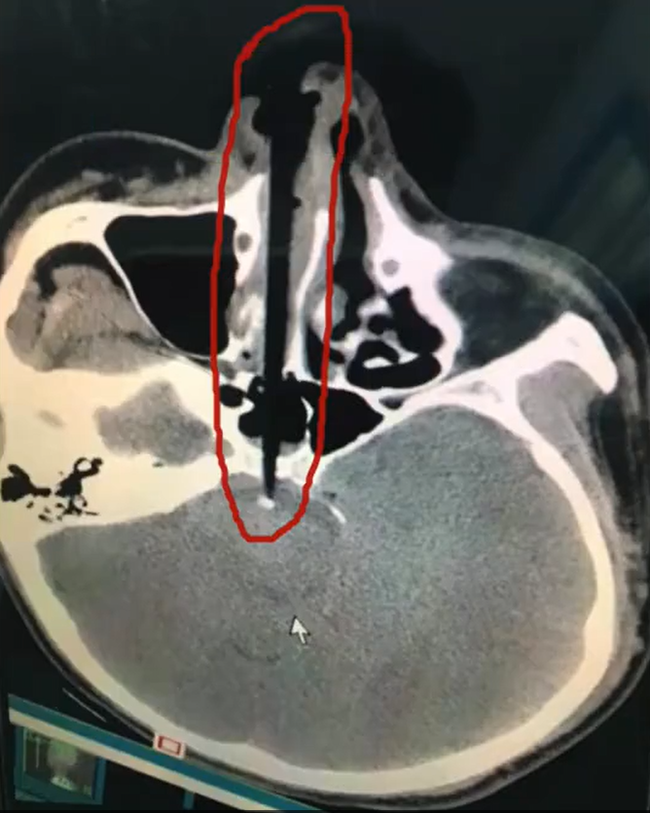

Nhưng điều tồi tệ nhất không phải là chiếc đũa đó vừa để ăn cơm mà lại dùng để ngoáy mũi. Khi anh ta đứng dậy, bỗng bị vấp ngã và mặt cắm xuống đất. Như mọi người có thể tưởng tượng, chiếc đũa 20cm đã cắm thẳng vào hốc mũi. Khi mọi người nghe thấy tiếng kêu thất thanh và quay trở lại phòng ăn, ai nấy đều hãi hùng trước cảnh tượng trước mắt.

Ngay lập tức, anh ta được đưa đến bệnh viện gần nhất, các bác sĩ tiến hành phẫu thuật cấp cứu vì sợ rằng bất kỳ chuyển động nhỏ nào cũng có thể khiến chiếc đũa đẩy sâu vào bên trong hộp sọ.